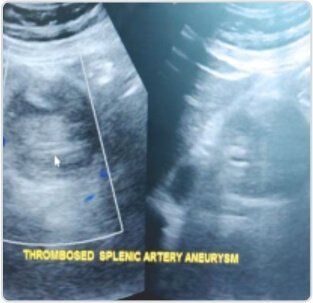

The aneurysm was treated with Endovascular technique. The distal outflow of the aneurysm was embolized by coils followed by occlusion of proximal flow into the aneurysm by placing Amplatzer vascular plug device in the proximal splenic artery. Check DSA revealed complete occlusion of the aneurysm with preserved flow into distal splenic artery and splenic perfusion via gastroepiploic and short gastric arteries. On Post-operative day 1, Doppler study revealed completely thrombosed aneurysm. The patient was discharged in pain-free state without any need for splenectomy.

Follow up Doppler scan post-operative day 1 revealed completely thrombosed aneurysm